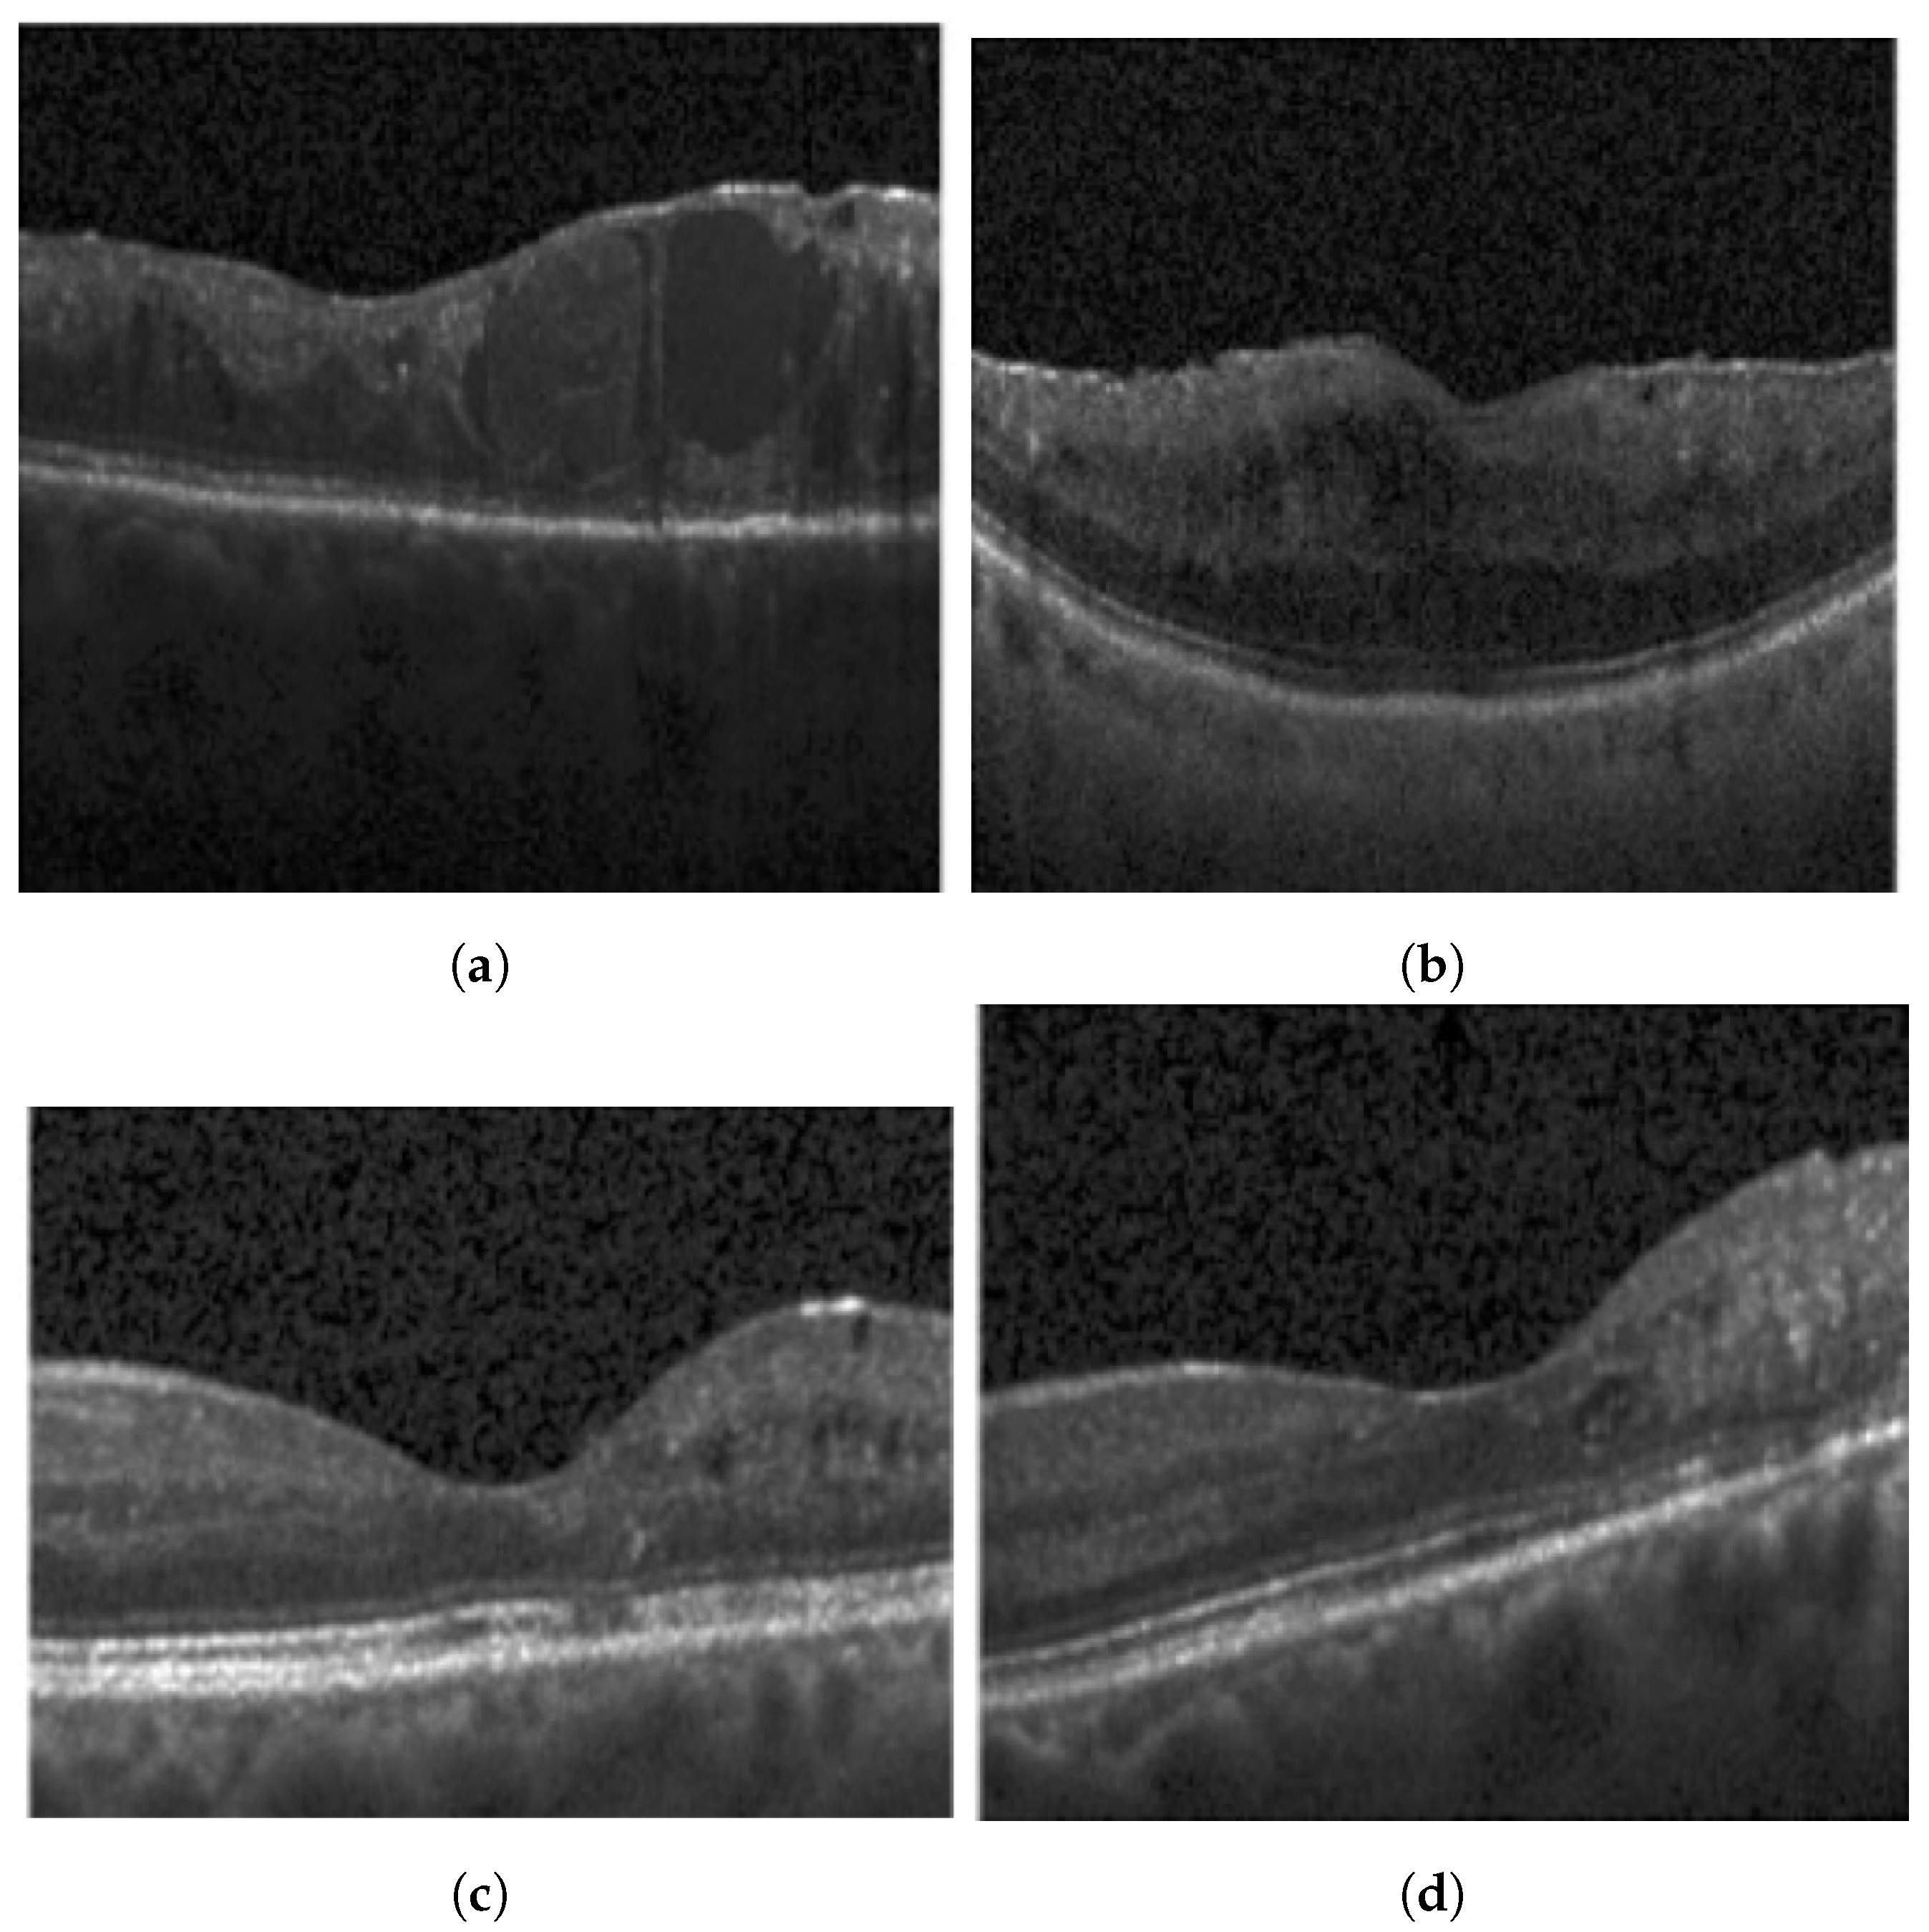

2.1. Disorganization of Retinal Inner Layers (DRIL)

3.1.1. Disorganization of Retinal Inner Layers (DRIL)

4.3.1. DRIL